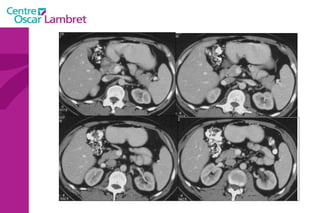

L’appareil urinaire L’appareil urinaire se compose des reins, des uretères et de la vessie. Les reins  sont rétro-péritonéaux : de part et d’autre du rachis entre T12 et L3. Fixés sous les côtes, ils sont en liaison avec l’artère rénale . Le rein possède une fonction secrétoire puis excrétoire à partir du pyelon, origine de l’uretère.

L’appareil urinaire

L’appareil urinaire Les uretères  se dirigent vers le bas, en avant et en dedans pour rejoindre la partie postéro supérieure de la vessie. On distingue 3 parties : L’uretère lombaire (12 cm) L’uretère iliaque (3 cm) L’uretère pelvienne (12 cm)

La vessie  : Elle recueille l’urine qui lui parvient par les uretères. L’urine est évacuée par l’urètre lors de la miction. L’appareil urinaire

Les surrénales  sont 2 glandes endocrines triangulaires situées au dessus des reins. Elles sont principalement responsables de la gestion des situations de stress via la synthèse de corticostéroïdes et de cathécolamines, entre autres le cortisol et l‘adrénaline.  Intérêt d’un balisage digestif pour l’étude de ces glandes L’appareil urinaire